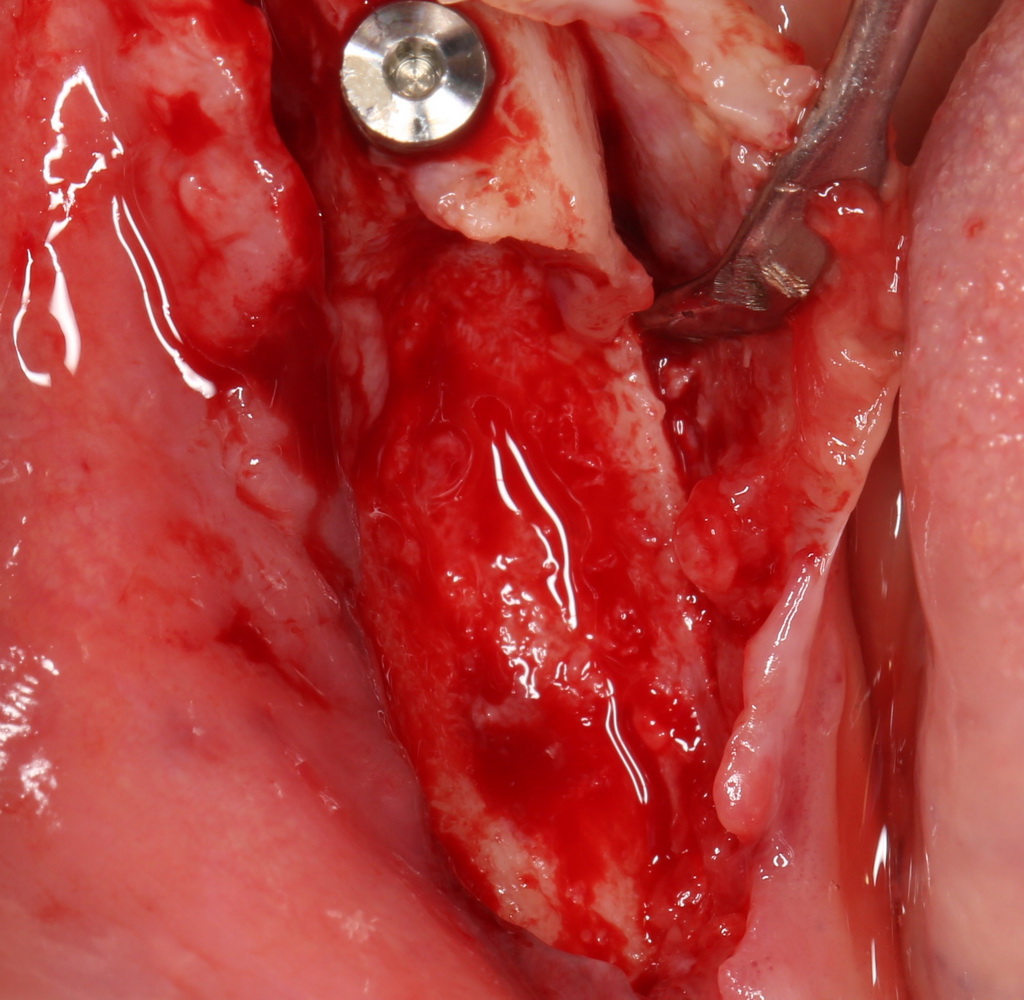

Например, в следующей ситуации:

Оставить так, как есть — это значит, сильно рисковать имплантом и объемом альвеолярного гребня — фактически, большая часть импланта пятого зуба «висит в воздухе». Поэтому получившуюся костную полость мы заполняем аутокостной стружкой в смеси с Bioss и закрываем коллагеновой мембраной BioGide: